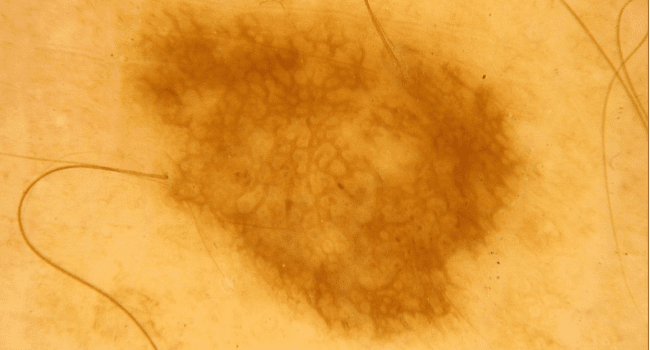

Zwykłe znamiona

Znane wszystkim zwykłe pieprzyki to inaczej znamiona barwnikowe powstałe w wyniku namnażania się komórek pigmentowych – głównie pod wpływem promieniowania UV. Większość z nich jest neutralna dla zdrowia i co najwyżej tworzy problem jako defekt kosmetyczny.

Zwykłe znamię barwnikowe - łagodny pieprzyk zdjęcie dermatologiczneZwykłe znamię barwnikowe - łagodny pieprzyk zdjęcie dermatologiczne

Zwykłe znamię barwnikowe - typowy pieprzyk zdjęcie medyczneZwykłe znamię barwnikowe - typowy pieprzyk zdjęcie medyczne

Zwykłe znamię barwnikowe - pieprzyk łagodny zdjęcie kliniczneZwykłe znamię barwnikowe - pieprzyk łagodny zdjęcie kliniczne

Zwykłe znamię barwnikowe - typowy pieprzyk zdjęcie dermatologiczneZwykłe znamię barwnikowe - typowy pieprzyk zdjęcie dermatologiczne

Zwykłe znamię barwnikowe - łagodny pieprzyk zdjęcie medyczneZwykłe znamię barwnikowe - łagodny pieprzyk zdjęcie medyczne

Zwykłe znamię barwnikowe - pieprzyk łagodny zdjęcie dermatologiczneZwykłe znamię barwnikowe - pieprzyk łagodny zdjęcie dermatologiczne